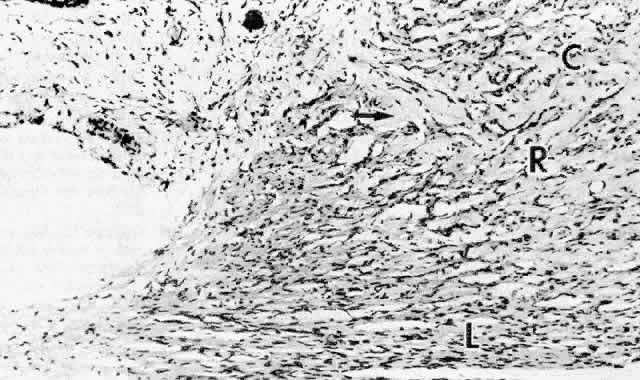

The ciliary muscle has a complex architecture, and its three dimensional organization and function have been difficult to visualize. Traditionally, the muscle is divided into three portions (Fig. 34): an outer longitudinal or meridional portion ( Brücke's muscle), a middle oblique portion (also called reticular or radial), and an inner circular component ( Müller's muscle). These regions are so interconnected that they were recognized early as designed to function like a single muscle mass when stimulated.37 Experimental evidence in humans, primates, and other mammals supports the view that the contracting ciliary muscle undergoes a shortening with anterior traction on the ora serrata region, and an inward and posterior pull on the scleral spur and trabeculum.6,38–40 Contraction of the oblique and circular portions in particular contributes a strong anterior and inward movement of the processes. The result is a well coordinated anterior-inward squeezing effect, displacing the processes toward the lens equator, and resulting in relaxation of zonular pull on the lens capsule. This inward movement of the ciliary processes has been dramatically shown by cinematography in primates after iridectomy.41

Fig. 34. Ciliary muscle showing circular (C), radial (R), and longitudinal (L) divisions and their relation to the scleral spur (ss) at age 2. A rare muscle bundle is present in the iris root. (hematoxylin-eosin, X 250)

The great bulk of the ciliary muscle lies in the anterior two thirds of the ciliary body (see Fig. 5). At the light microscopic level in the child, the longitudinal muscle shows a primary attachment to the scleral spur and to the outer corneoscleral and uveal trabecular meshwork, while the oblique radial fibers have more connection to the inner uveal meshwork (see Fig. 34). The circular muscle attachments are primarily to the adjacent ciliary and iris root stroma. During aging the addition of significant fibrous tissue and hyaline greatly increases the bulk of the radial and circular muscles (Fig. 36) but not the longitudinal muscle. Tamm, Tamm, and Rohen44 found that connective tissue comprised about half of the oblique muscle in the 50- to 60-year-old age group. The circular muscle was also significantly increased in area and partially separated from the oblique muscle by this connective tissue, which was continuous with hyaline in the processes. The overall effect of aging on the ciliary muscle made it shorter in length and greater in area with a prominence of the circular muscle, resulting in a forward and inward configuration resembling the accommodated state. Others have described some atrophy of the muscle with decreased nuclei, particularly in the circular muscle and over the age of 40 years.45

Fig. 36. Dense pale hyaline deposition (arrow) between the circular (C) and radial (R) but not the longitudinal (L) muscle bundles of a 64-year-old patient. Compare with Figure 34 from 2-year-old child. (hematoxylin-eosin, X 250)